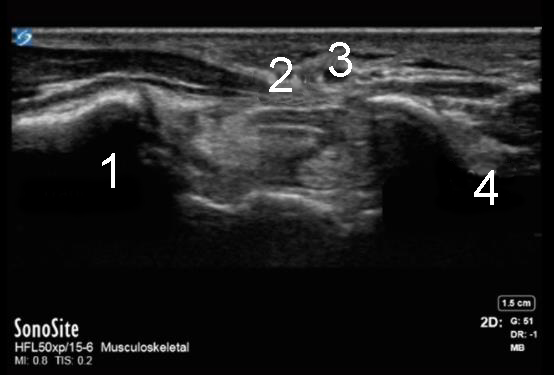

Wrist Distal Carpal Tunnel Image

Trapezium

Median Nerve

Artery

Hook of Hamate